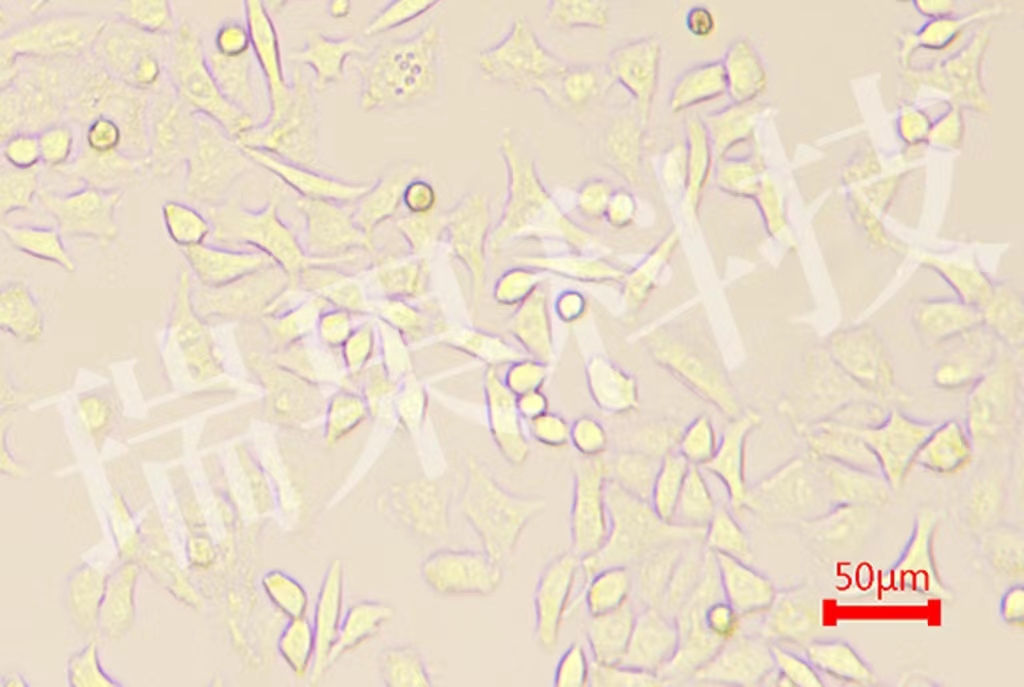

免疫細胞亞群的細分和鑒定已成為當代免疫學發展呈現的新特點...